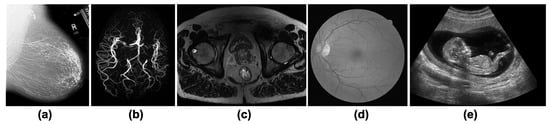

2.1. Medical Digital Databases

2.1.1. Full-Digital Mammography Database

2.1.2. Magnetic Resonance Angiography (MRA) Vascular Brain Database

2.1.3. MRI Prostate Database

2.1.4. Digital Retinal Database

2.1.5. Ultrasound Database